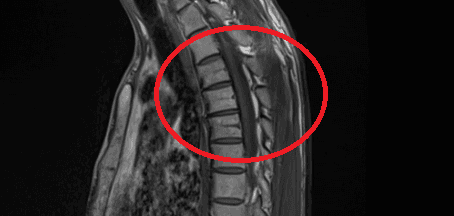

안녕하세요. 남희성 의사입니다.

이런 경우에 골절이 아닌지 오해하시는 경우가 많은데 골절이 아닙니다.

골절의 경우에는 T1 영상에서 조영이 떨어지고 fat suppression T2 영상에서 조영이 증가하는 소견을 확인해야합니다.

골절이 아니면 왜 저렇게 보이는지 까지는 제가 잘 모르지만 저 소견을 이상소견으로 보이는 않습니다.